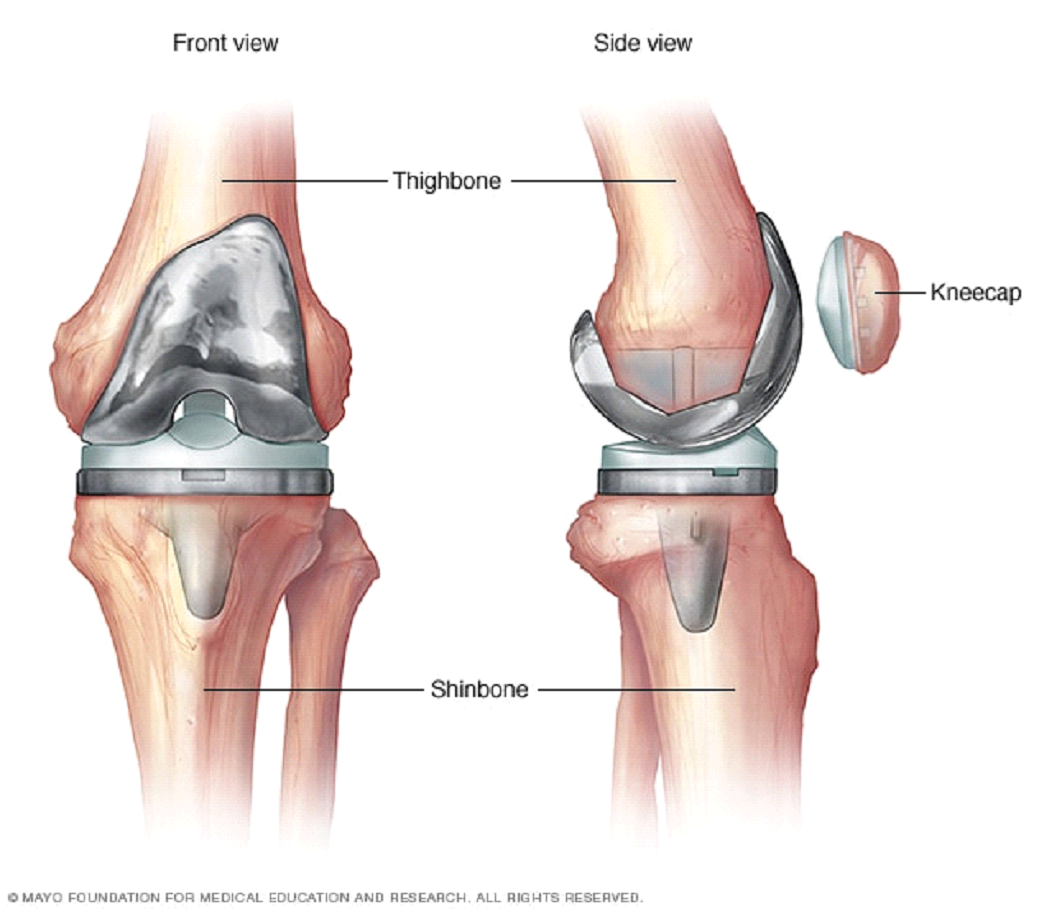

When to Consider Surgery

Surgery may be considered if Pain severely limits daily activities Inability to get out of bed, go to the washroom.

Considered only for severe cases after optimal non-surgical care;Arthroscopy is not recommended for uncomplicated OA